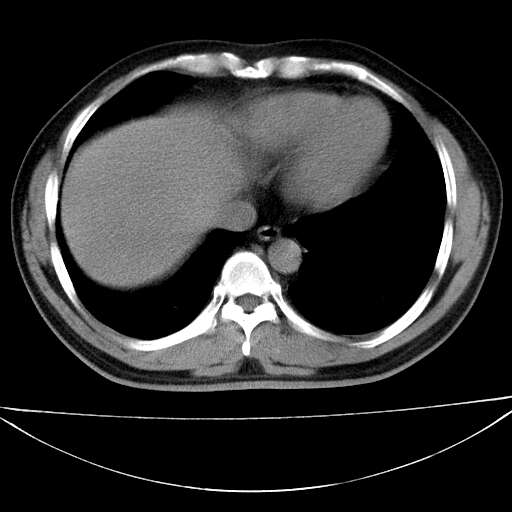

标题: CT21921:腹膜后腔肿物。患者男39Y。体检。增强扫描时间欠准

左侧膈肌脚外缘见一结节样软组织影,密度较均匀,与胸膜关系稍密切,增强轻度强化;考虑来自胸膜良性病变(胸膜纤维瘤可能)。建议加扫胸部ct检查。

2、左下膈肌脚外缘结节状病变,与胸膜交界面呈锐角,胸膜下脂肪线可见,定位于肺内,考虑支气管囊肿或肺隔离征可能性大。

膈疝

左肋隔角占位,考虑胸膜间皮瘤

1)考虑左肺下叶后基底段(或左下胸后壁胸膜)软组织团块,性质待定;建议行进一步检查。2)左肾结石。

左膈肌连续性中断,左侧膈疝可能性大.

左膈肌角后腹膜腔见肿物影,其内见脂肪密度灶及软组织密度灶,强化不明显。病灶大部在后腹膜内。考虑异位嗜铬细胞瘤或脂肪肉瘤、畸胎瘤

考虑左肺下叶后基底段肺隔离症?胸膜间皮瘤?